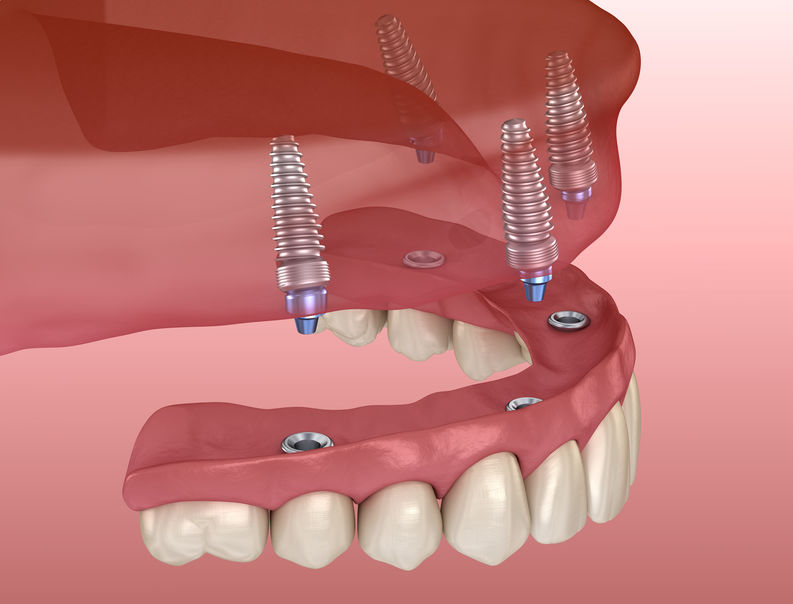

Пошаговое руководство по установке съёмного протеза на импланты